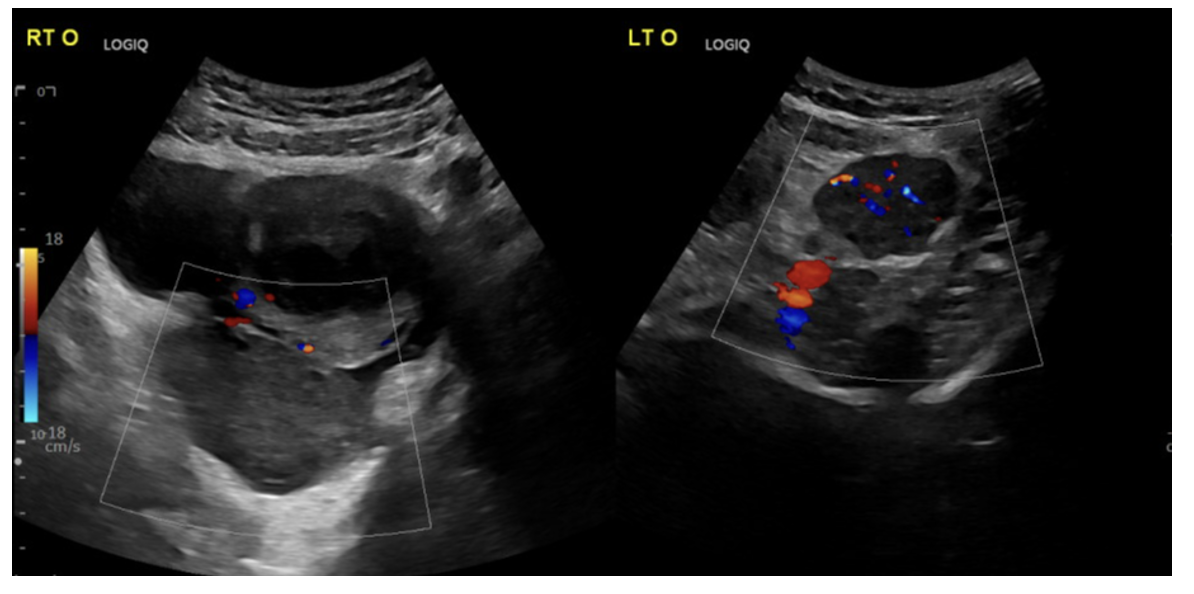

Ultrasound with color Doppler (transabdominal + transvaginal).

Doppler considerations:

Decreased/absent arterial flow → poor sensitivity (dual blood supply, late finding).

If present → PPV ~100%.

Key ultrasound finding:

“Whirlpool sign” (twisted vascular pedicle) (sensitivity ~65%, specificity ~91% (Garde et al., 2022))

Normal Doppler doesn’t rule it out (dual blood supply).

Whirlpool sign = highly specific → act fast.